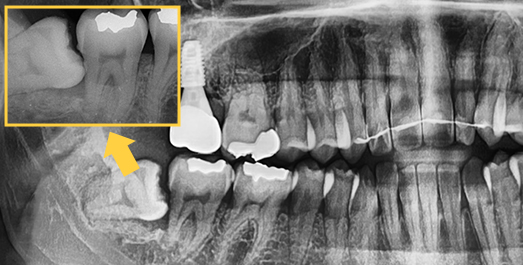

사랑니는 똑바로 나는 경우도 있지만 비스듬하거나 수평으로 나기도 하고 치아 전체가 매몰된 채로 있기도 합니다. 제대로 나지 않은 사랑니는 치열을 뒤틀리게 하고, 칫솔질이 쉽지 않아 주변 어금니를 썩게 만들기 때문에 발치하는 것이 좋습니다.

• 수평으로

숨어있는 사랑니

• 각도를 가지고

• 수직으로